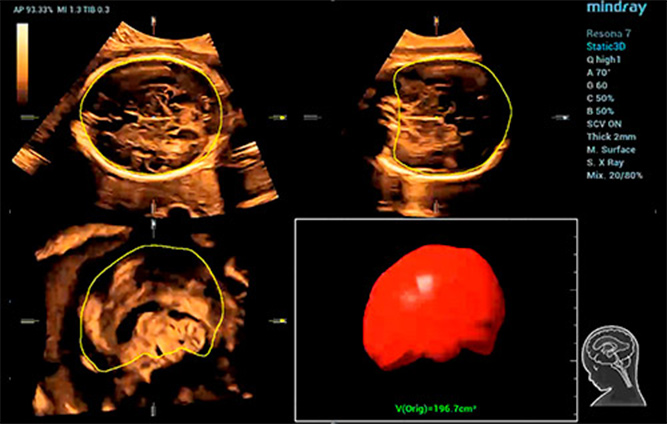

Smart Planes CNS

Smart ICV: Automatische berekening van intracraniaal volume